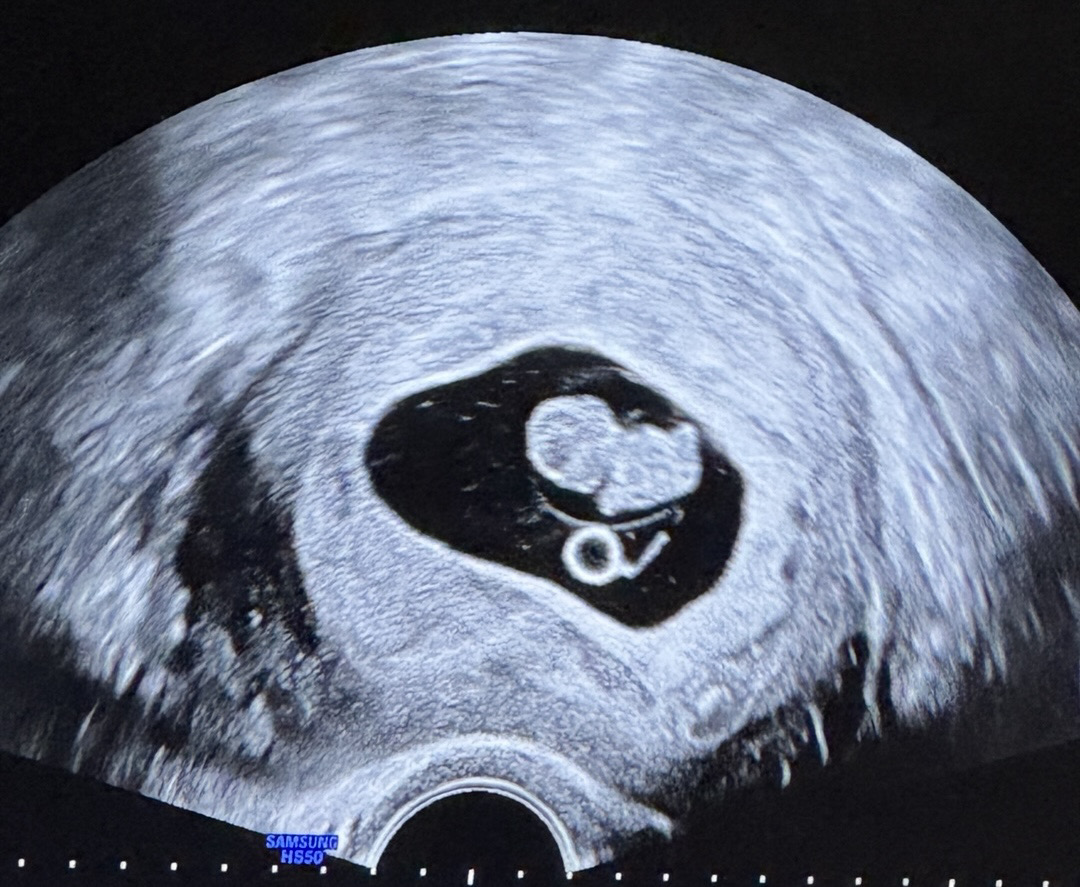

난황 아껴먹는(?) 아기

8주2일쯤 되는 초음파로 2등신 눈사람에 팔다리 보고왔는데 5주때 봤던 난황이 거의 그대로 있어요..! 남편이 애기가 난황 아껴먹는다고 그러는데 왜 난황이 줄거나 없어지지 않을까요? 혹시 저처럼 8주 넘었는데 난황 그대로 있는분도 계실까요?

저 10주찬데 아직 난황보여요! 의사쌤말로는 난황 없어지는데 한달정도 시간이 걸린대요!

저도 9주차에 봤는데 난황 그대로 있었어요 ㅋㅋㅋ

그러게욬ㅋㅋ 저 엊그제 9주차 초음파에서도 난황 사이즈가 그대로더라고요ㅎㅎ 그래도 아기는 잘 크고 있다고 합니다..!